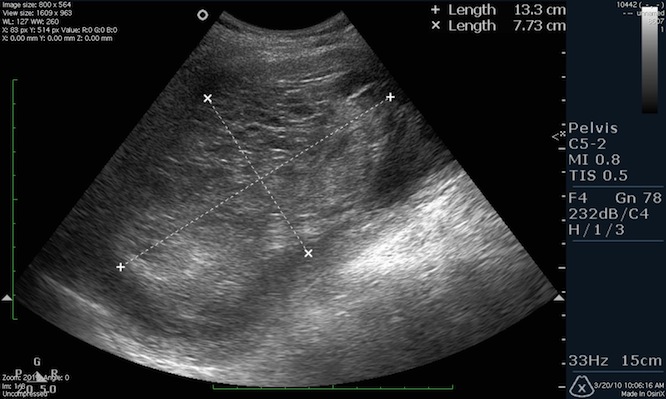

Ультразвуковое исследование покажет размеры матки, а опытный врач объяснит, каковы нормы ее размеров во время беременности, после родов и у девственниц. Фото УЗИ иллюстрирует размеры шейки матки, яичников и то, как выглядит матка, а врач даст полное описание изображению.

Осмотру подвергается тело матки, яичники, фаллопиевы трубы. Гинеколог при осмотре оценивает состояние матки, яичников и яйцеводов. Диагностике подлежит структура, форма, размер, толщина стенок, эхогенность, наличие визуально выраженных отклонений от нормы. Помимо этого, смотрят состояние шейки матки, ее длину и плотность.

При обследовании изучается расположение матки, ее форма, размеры и толщина стенок. Определяется состояние яичников и корректность их работы, проверяется наличие новообразований и жидкости в брюшной полости.

Размеры матки в норме у женщин, расположение органа, толщину эндометрия и расположение яичников позволяет наиболее точно выявить трансвагинальная диагностика. Для этого датчик, который представляет собой пластиковый стержень 12 см в длину, вводится на небольшую глубину.

Норма обследования матки по УЗИ у женщин детородного возраста и в постменопаузе

Размеры матки в норме у женщин отличаются в зависимости от возраста, количества беременностей, абортов и гормонального фона. Специалисты измеряют длину и ширину матки, указывают толщину стенок.

Женщины детородного возраста имеют матку следующих размеров:

- длина – до 70 мм;

- ширина – до 60 мм;

- толщина стенок – до 42 мм.

Если женщина не рожала и не беременела, длина матки 47 мм, у рожавших показатели возрастают до 61 мм. При этом с каждой беременностью длина матки и ее ширина увеличиваются. Когда были беременности, но без родов, длина органа будет в пределах 54 мм.